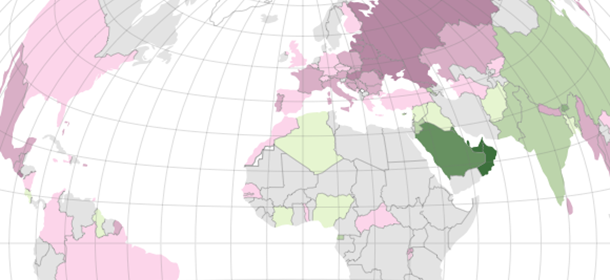

Negli Stati Uniti l’approccio seguito da tempo per tenere sotto controllo i rischi (screening) consiste nel sottoporsi periodicamente a una colonscopia completa, a partire dai 45 anni. In Europa e in buona parte del resto del mondo le colonscopie sono invece utilizzate di rado come strumento per fare lo screening, perché sono costose, poco piacevoli e invasive per i pazienti e soggette a qualche rischio per quanto raro.

Sebbene non ci sia uno scontro di civiltà intorno allo screening per il cancro al colon retto, la differenza di posizioni è comunque marcata: i gastroenterologi negli Stati Uniti sono da decenni per la colonscopia periodica praticamente per tutti, mentre in Europa si preferiscono altri esami, meno invasivi e più economici. Ma che cosa funziona meglio? Come dimostra il grande studio su cui gli esperti litigano da quasi un anno, trovare una risposta è estremamente complicato e contorto, più delle anse e circonvoluzioni della decina di metri del nostro apparato digerente, dove inizia il nostro viaggio.

Negli Stati Uniti la colonscopia è ritenuto l’esame più importante, o “di elezione” come dicono i medici, per fare screening nella popolazione in generale. Per questo la procedura viene raccomandata alle persone più a rischio, di solito dai 45 anni in poi, e si consiglia di ripeterla periodicamente in modo da andare a caccia dei polipi. In Europa e in diverse altre parti del mondo l’approccio è diverso ed è basato quasi sempre su esami meno invasivi e costosi.

Il confronto si è sviluppato lungo diversi filoni, quasi sempre evidenziando una certa differenza di vedute tra gli Stati Uniti, dove si fanno molte colonscopie, e l’Europa dove se ne fanno poche (ci sono differenze anche rispetto ad altri paesi, ma Stati Uniti ed Europa sono più confrontabili e soprattutto hanno raccolto nel tempo maggiori quantità di dati).